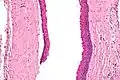

Odontogenic keratocysts have a diagnostic histological appearance. Under the microscope, OKCs vaguely resemble keratinized squamous epithelium;[14] however, they lack rete ridges and often have an artifactual separation from their basement membrane.[2]

The fibrous wall of the cyst is usually thin and uninflamed. The epithelial lining is thin with even thickness and parakeratinised with columnar cells in the basal layer which have focal reverse polarisation (nuclei are on the opposite pole of the cell).[12] The basal cells are an indication of the odontogenic origin as they resemble pre-ameloblasts. The epithelium can separate from the wall, resulting in islands of epithelium. These can go on to form 'satellite' or 'daughter' cysts, leading to an overall multilocular cyst.[9] Presence of daughter cysts is particularly seen in those with NBCCS.[12] Inflamed cysts show hyperplastic epithelium which is no longer characteristic of OKCs and can have resemblance to radicular cysts instead. Due to areas of focal inflammation, a larger biopsy is required for correct diagnosis of odontogenic keratocysts.[9]

Intermediate magnification of an odontogenic keratocyst showing a folded cyst.

Intermediate magnification of an odontogenic keratocyst